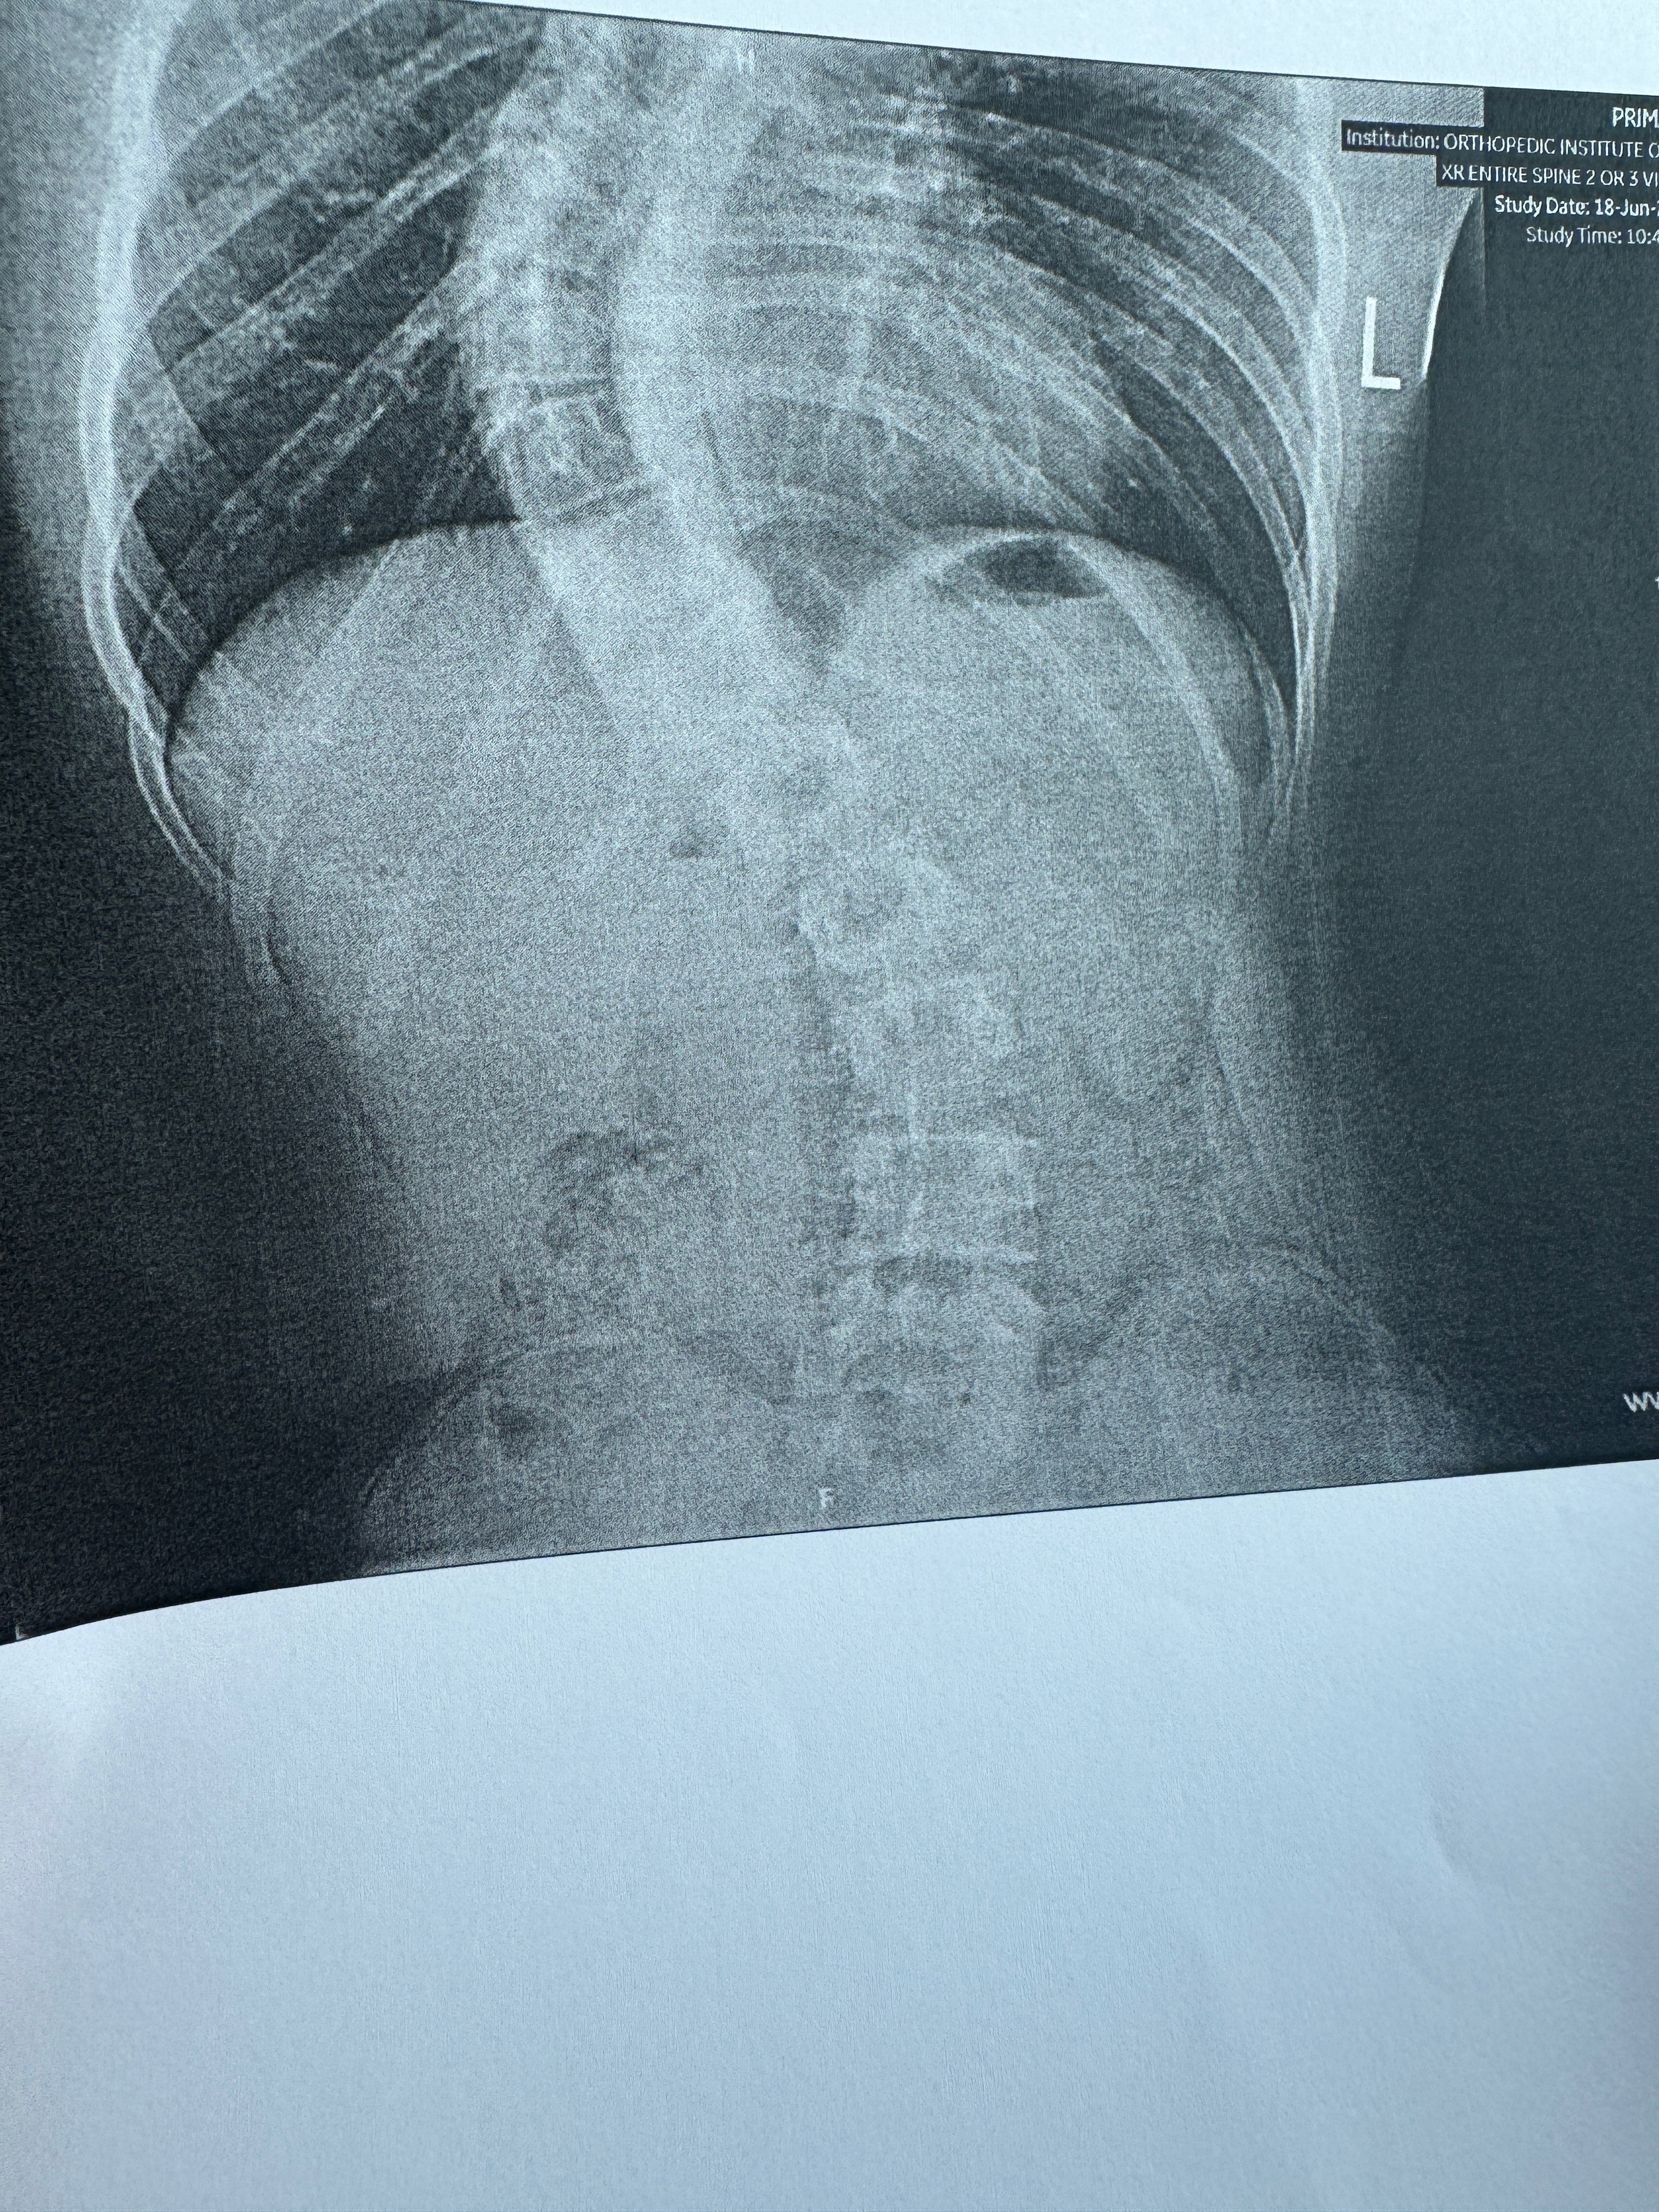

The cover photos below are of a case of severe scoliosis in Jaden. Jaden is a 17 year old autistic student in the 10th grade at Annville-Cleona, who truly needs us right now. His spine curvature went from 65° in May to 75° in August, so this issue is progressing rapidly.

The surgeon has recommended that they do rods, plates, screws, and a bone graft to hold everything in place. the worst part is that this may not be the only surgery he has to endure in the next few years.